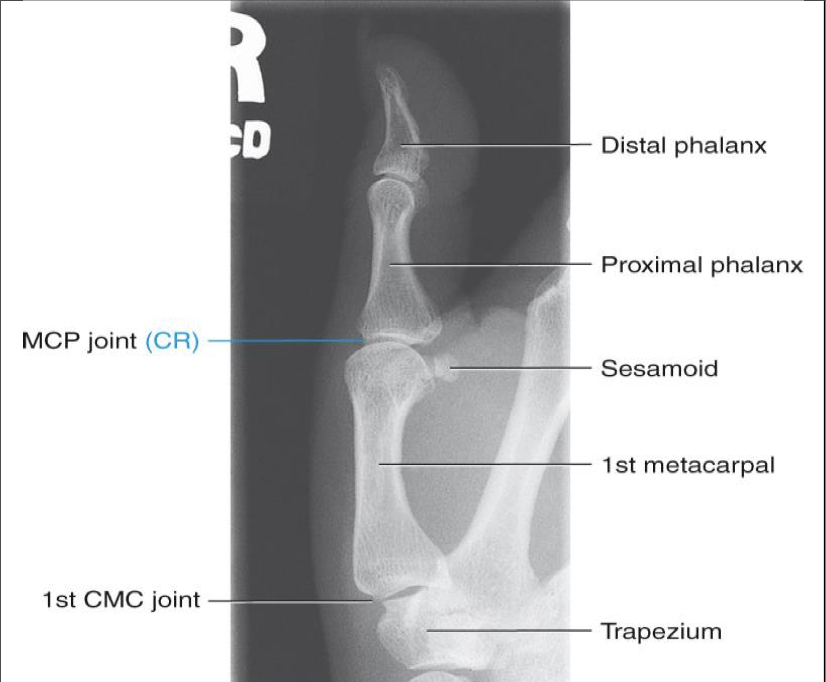

Lateral Thumb ( 1st Digit)

Evaluation Criteria for Lateral Thumb ( 1st Digit)

• Entire thumb demonstrated including trapezium

• Minimal overlap of bases of 1st and 2nd metacarpals

• Center of field at first MCP joint

• Increased concavity of phalanges on anterior (finger) side

• Decreased concavity on posterior side